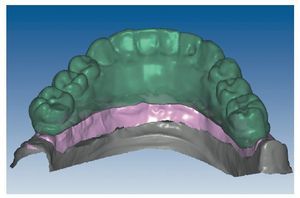

Mediante el uso de un escáner óptico de luz estructurada, los protocolos CAD registran los primeros datos relativos al modelo maestro con las correspondientes posiciones de implante (figs. 87 y 92). En el siguiente paso tiene lugar la digitalización de la planificación, previamente realizada en cera de escaneo matificada, de la restauración definitiva (figs. 88, 90 y 93). La subsiguiente conciliación de los datos mediante el uso del software de diseño dental permite al protésico planificar virtualmente el resto del procedimiento (figs. 89 y 91, 94 a 96) a partir del diseño de las estructuras (figs. 97 y 98).

Fig. 91. El diseño definitivo de la estructura para el maxilar superior.

Figs. 96 a 98. El diseño definitivo de la estructura del maxilar inferior, desde distintas perspectivas.

Una vez aprobada la planificación, mediante el software CAD se transmiten los datos en formato STL (Standard Transformation Language o Stereolithography Language) a otro software CAM, el cual procesa nuevamente los datos suministrados para enviarlos en «idioma de máquina» a la fresadora (Zfx, ULTRASONIC 20, Denttec KG-SAS, Gargazon, Italia) encargada de confeccionar la estructura de titanio (figs. 98 y 99). La utilización de fresadoras industriales de cinco ejes para la confección de este tipo de prótesis garantiza un éxito seguro en cuanto a precisión de ajuste y pasivización, y evita casi todos los riesgos que pueden aparecer durante el colado protésico clásico.

Pese a ello, es importante someter las estructuras a un control visual y mecánico, a fin de corregir eventuales discrepancias menores (figs. 99 a 102). A continuación se procede al montaje utilizando dientes protésicos prefabricados de composite (SR Phonares NHC, Ivoclar Vivadent, Ellwangen, Alemania), los cuales reproducen el tipo funcional correspondiente en virtud de sus propiedades morfológicas y estructurales y se integran armoniosamente en cuanto a su longitud dental (figs. 103 a 105). Durante la comprobación de las restauraciones protésicas, se evalúan clínica y radiológicamente ante todo la pasividad y la precisión del ajuste de la estructura. Acto seguido se lleva a cabo una comprobación de la oclusión y de la dimensión vertical, del estado de las prótesis y del tejido blando en la cresta alveolar, así como la verificación del espacio libre lingual, incluida la fonación, y el apoyo de los labios y las mejillas (figs. 106 y 107). También se debe comprobar la facilidad de higiene de la restauración de acuerdo con las habilidades manuales del paciente. A continuación se debe verificar la posición tridimensional de los dientes anteriores con los labios cerrados y durante la sonrisa, así como el aspecto global de la rehabilitación protésica.